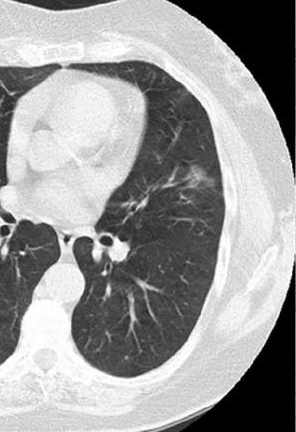

磨玻璃结节

磨玻璃结节的病因很复杂。它可以由炎性肿瘤、肺结核或恶性病变引起。因此,在确定我们存在这种现象之后,我们决不能掉以轻心。我们应该及时进行进一步的检查,以避免疾病的延误,而且得不偿失。如果我们在检查后发现它是由炎性肿瘤引起的,我们不必太担心。只要我们治疗炎症,肿瘤就会在病情恢复后自行消退。如果是肺结核引起的,不要太惊慌。虽然这种疾病是持久性的,但只要患者及时服用抗结核药物,注意生活护理,也可以有效控制。

但是,如果患者的肺玻璃结节是由恶性病变引起的,我们应该给予足够的重视,因为这种情况对身体非常有害,不仅不会自行消失,而且恶性细胞也会扩散和转移,这将给治疗带来很大困难。因此,我们应该及时手术,尽快切除病变组织。如果疾病发展到中晚期,我们还应该进行化疗和放疗,以清除体内的癌细胞,并尽可能控制疾病的发展。同时,我们也应该注意生活中的护理:我们应该及时服用靶向药物和免疫药物,我们还可以服用相关的中药来调节身体,这对提高疾病的治愈率有很大帮助。

磨玻璃结节的病因很复杂。在炎症性肿瘤和肺结核中,它们可以在病情得到控制后消失。然而,对于恶性病变,它不会自行消失,还会导致疾病的传播和转移。